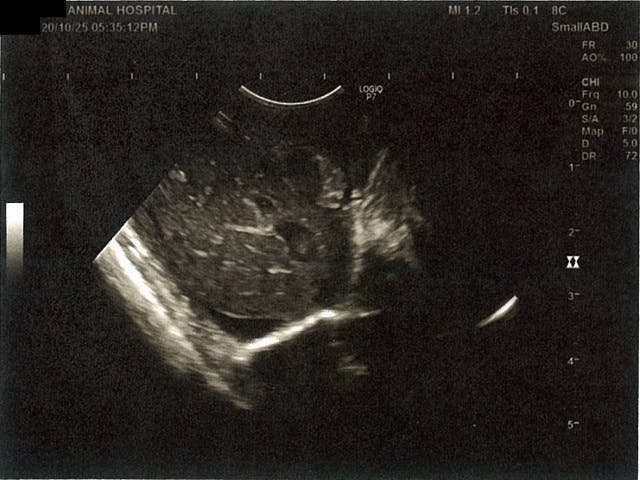

《心臓周りの胸部以外の全ての腹部で腹水がみられるとの診断です》

大網という部分で内臓を包む膜のようなものです。その周りに腹水が溜まっています。

膀胱周りに腹水が確認できるエコー写真